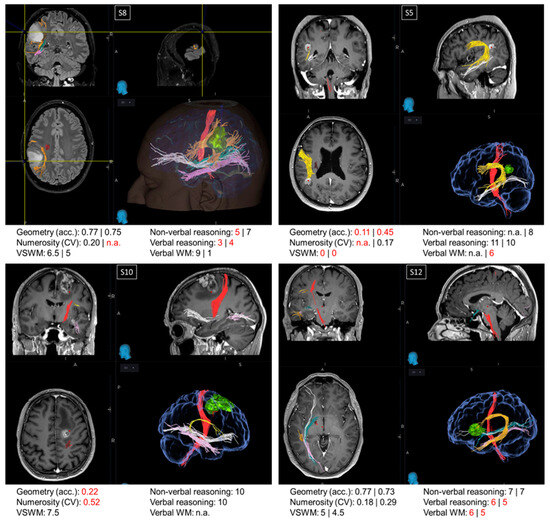

| S5 | Left AG (22 × 22 × 22) | Ca | 45 | n.a. 8 | 0 0 | 11 0 | n.a. 6 | n.a. 0.17 | 0.11 0.45 | 0.12 0.42 | 0.10 0.48 |

| S8 | Left parietal lobe (30 × 28 × 34) | O | 28 | 5 7 | 6.5 5 | 3 4 | 9 1 | 0.2 n.a. | 0.77 0.75 | 0.71 0.83 | 0.80 0.70 |

| S10 | Right frontal lobe (MFG/IFG) (40 × 29 × 36) | G | 64 | 10 | 7.5 | 10 | n.a. | 0.52 | 0.22 | 0.25 | 0.20 |

| S12 | Left IFG (fronto-opercular) (10 × 12 × 10) | G | 54 | 77 | 5 4.5 | 6 5 | 6 5 | 0.18 0.29 | 0.77 0.73 | 0.79 0.75 | 0.75 0.73 |